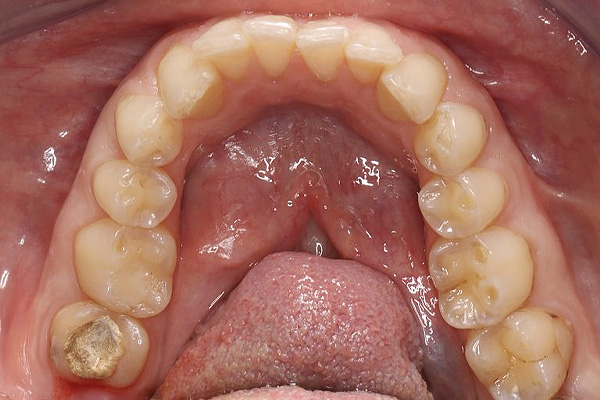

Terapinis gydymas Terapinis dantų gydymas – tai viena svarbiausių procedūrų, skirta suaugusiųjų ir vaikų burnos sveikatai išsaugoti. Šio gydymo metu efektyviai šalinamas dantų ėduonis (kariesas), restauruojami nuskilę ar nulūžę dantys bei keičiamos senos, nehermetiškos plombos. Taip pat atliekamas pleištinių defektų gydymas, padedantis apsaugoti apsinuoginusius dantų kaklelius nuo jautrumo ir tolesnio dylimo. Naudojant modernias medžiagas, atkuriama natūrali danties forma, spalva ir pilnavertė funkcija.Kas yra dantų ėduonis?Viena iš labiausiai paplitusių dantų ligų – dantų ėduonis (dar vadinama kariesu), kuri atsiranda dėl rūgščių dantų apnašų ir mikroorganizmų sąveikos. Laiku pastebėtas ėduonis išvalomas iki sveikų danties audinių, vėliau ertmė padengiama plombine medžiaga anatomiškai atkuriant danties formą ir funkciją. Pastebėjus ir laiku užkirtus kelią ėduonies atsiradimui ir plitimui – išvengsite didesnių problemų ateityje.Kodėl reikalingas dantų terapinis gydymas?Atsiradęs dantų jautrumas – kai dantys tampa jautrūs dėl dantenų atsitraukimo ar emalio nusidėvėjimo, tai gali sukelti diskomfortą valgant karštą, šaltą ar saldų maistą.Jei jaučiate kramtymo problemas – neteisingas dantų sukandimas gali sukelti įtampą žandikauliuose, galvos skausmus ir dantų dilimą.Dantų estetika – norint pagerinti dantų išvaizdą dėl estetikos priežasčių, pavyzdžiui, dėl tamsių dantų, netaisyklingos formos ar dydžio.Dantų skilimai ir lūžiai.Sąkandžio pakėlimas pagal pavaškavimąSakandžio pakėlimas pagal pavaskavimą (dar vadinamas „okliuzijos pakėlimu“) dažnai taikomas odontologijoje, kai siekiama koreguoti kramtomąją funkciją ir pagerinti sukandimo liniją.Kodėl reikalinga?Jei jaučiate dantų skausmą ar diskomfortą;Jaučiate įsitempusius žandikaulio ar veido kramtomuosius raumenis;Atsirado galvos skausmai;Jei jaučiate apatinio žandikaulio judėjimo sutrikimus.Atliekant sąkandžio pakėlimą gydytojas odontologas pirmiausia turi nusiimti paciento dantų atspaudą ir jį nusiųsti dantų technikams, kad būtų pagamintas pavaškavimas – kuris reikalingas gydytojui atkuriant dantų aukštį ir funkciją pagal dantų anatomiją.Dažnai užduodami klausimai (D.U.K.)Kiek laiko galima būti su laikina plomba?Laikina plomba dažniausiai dedama, kai tarp vizitų yra tarpai, ar po endodontinio gydymo keičiant į nuolatinę. Laikina plomba neturėti būti ilgiau nei 2-4 savaites, nes ilgainiui ji tirspta ir tampa pralaidi, gali iškristi.Kada galima valgyti po danties plombavimo?Jei buvo naudota vietinė nejautra, tuomet rekomenduojama palaukti, kol baigsis jos poveikis, kad nesukramtytumėte vidinės žando pusės. Jei nebuvo nejautros, tuomet galite valgyti iš karto, tačiau gydytojas odontologas perduos vis informaciją po vizito.Kiek kainuoja vieno danties plomba?Tiksli kaina priklauso nuo keleto veiksnių: pažeidimo gylio, plombinės medžiagos sunaudojamo kiekio, bei vizito metu naudojamų papildomų medžiagų ir priemonių (nuskausminimo, rentgeno nuotraukų ir t.t.)Paslaugos specialistai Visi Kaunas Vilkaviškis Visi specialistai Žilvinas Budrevičius Estetinių restauracijų specialistas, gyd. odontologasKaunas Inga Linkytė – Sližienė Estetinių restauracijų specialistė, gyd. odontologėKaunas Marius Kanopa Protezuojantis gyd. odontologasKaunas Odeta Bardijevskienė Estetinių restauracijų specialistė, gyd. odontologėKaunas Agnė Koncevičiūtė Estetinių restauracijų specialistė, gyd. odontologėKaunas, Vilnius Viktorija Šimkutė Dantų tiesinimo kapomis specialistė, gyd. odontologėKaunas Simona Pėčelytė Gyd. odontologė, specializuojasi vaikų ir suaugusių dantų gydymeKaunas, Vilnius Simona Pluščiauskaitė Gyd. odontologė, specializuojasi suaugusių dantų gydyme bei dantų šalinimeKaunas, Vilkaviškis Žemyna Binevičiūtė Gyd. odontologėKaunas Arūnė Mencevičienė Gyd. odontologėKaunas Austėja Valaškevičiūtė Gyd. odontologėKaunas Indrė Stočkė Gyd. odontologėVilkaviškis Lijana Linkevičiūtė Gyd. odontologė, specializuojasi vaikų ir suaugusių dantų gydymeVilkaviškis Žilvinas Budrevičius Estetinių restauracijų specialistas, gyd. odontologasKaunas Inga Linkytė – Sližienė Estetinių restauracijų specialistė, gyd. odontologėKaunas Marius Kanopa Protezuojantis gyd. odontologasKaunas Odeta Bardijevskienė Estetinių restauracijų specialistė, gyd. odontologėKaunas Agnė Koncevičiūtė Estetinių restauracijų specialistė, gyd. odontologėKaunas, Vilnius Viktorija Šimkutė Dantų tiesinimo kapomis specialistė, gyd. odontologėKaunas Simona Pėčelytė Gyd. odontologė, specializuojasi vaikų ir suaugusių dantų gydymeKaunas, Vilnius Simona Pluščiauskaitė Gyd. odontologė, specializuojasi suaugusių dantų gydyme bei dantų šalinimeKaunas, Vilkaviškis Žemyna Binevičiūtė Gyd. odontologėKaunas Arūnė Mencevičienė Gyd. odontologėKaunas Austėja Valaškevičiūtė Gyd. odontologėKaunas Simona Pluščiauskaitė Gyd. odontologė, specializuojasi suaugusių dantų gydyme bei dantų šalinimeKaunas, Vilkaviškis Indrė Stočkė Gyd. odontologėVilkaviškis Lijana Linkevičiūtė Gyd. odontologė, specializuojasi vaikų ir suaugusių dantų gydymeVilkaviškis Registruokitės terapiniam dantų gydymui ir pasirūpinkite savo šypsena su mūsų specialistų pagalba! Internetu +370 444 77777